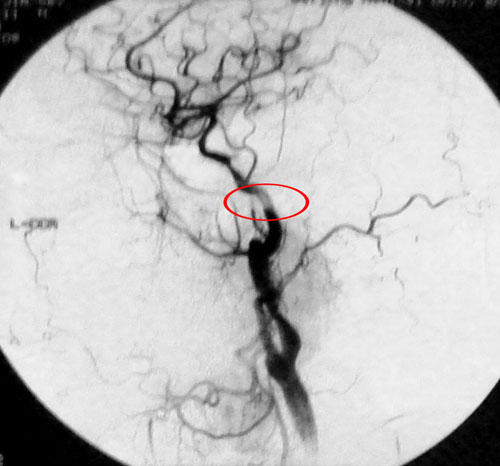

患者一:王某某,男性,52 岁,主因右眼视物不清7个月就诊。既往有II型糖尿病史14年,高血压史2年(3级),高甘油三酯血症。眼科检查:右眼玻璃体出血6个月,1个月前眼底有出血,视力仅0.2。左眼视网膜剥脱。1年前曾行白内障手术。房角3、6、9点新生血管。2008年9月8日在局麻下行颈动脉及眼动脉造影示:右侧颈内动脉起始部后壁斑块形成,局部管腔狭窄约50%,双侧眼动脉起始段狭窄约70%-80%。左侧血管虹吸部亦见狭窄。诊断:1、高血压病(药物控制后正常,极高危)2、2型糖尿病3、颈动脉粥样硬化症4、眼底出血5、高甘油三酯血症。(下图分别为其左侧和右侧颈动脉分叉DSA显像图)

该患者的颈内动脉管腔狭窄,影响了眼动脉的供血,行CEA手术取出斑块可以改善患者的症状。2008年9月28日,王某顺利接受了右侧颈内动脉内膜剥脱术。术后视力明显改善,右房角新生血管消退,视力提高,视物不清症状消失。半年后复查时其视力已恢复至0.4。

左侧颈动脉

右侧颈动脉